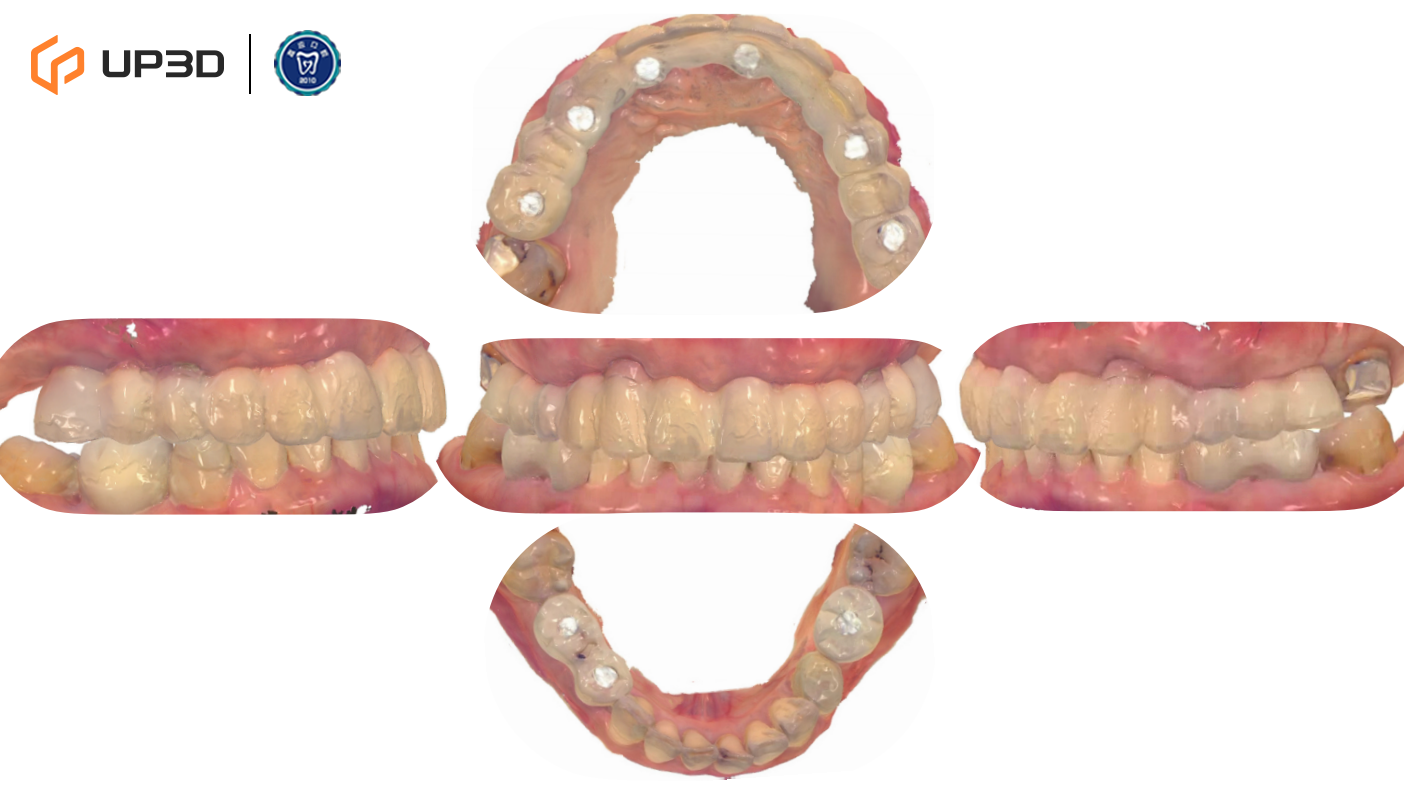

2.1 Intraoral Findings and Intraoral Scan Assessment

A digital intraoral scan (IOS) was used to capture maxillary and mandibular models. Clinical findings included multiple missing teeth, disordered dentition, and occlusal collapse with reduced facial support. Bone volume was limited in certain regions. The 3D scan clearly presented tooth morphology, soft tissue contours, and occlusal relationships—providing accurate data for subsequent digital implant planning.